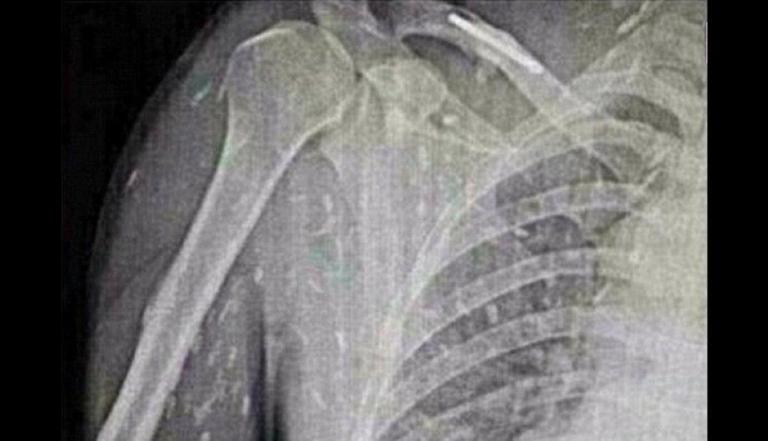

Ele relatou que esses sintomas já estavam acontecendo há uma semana. Depois de realizarem uma endoscopia, os médicos descobriram que havia larvas do gênero Anisakis dentro do estômago dele.

Tratar as pessoas com anisaquíase é apenas possível através da endoscopia ou cirurgia para remover o verme.

Neste caso o paciente somente uma endoscopia foi necessária para ele não sentir mais os incômodos. A anisaquíase é uma doença comum no Japão, devido aos hábitos alimentares das pessoas, como o consumo de sushi.